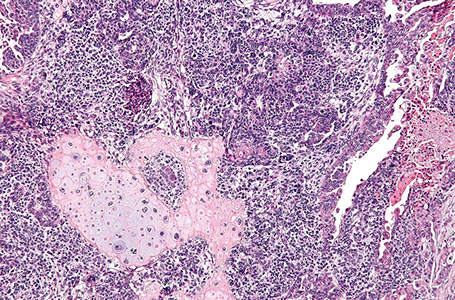

Undifferentiated / dedifferentiated Carcinoma

Rare, 2 tumor subtypes, usually a mix of emdometriooid AC and medium-sized monotonous epithelial cells in solid pattern, but can have variety of other cell types and most have some necrosis

Micro: eccentric nucleo, vesicular chromatin

IHC: focal PanCK + (may be diffuse), focal EMA+, neg Pax8

Genes: 1/2 have MSI c MLH1 promoter methylation and MLH1 / PMS2 loss of expression

Dedifferentiated carcinoma